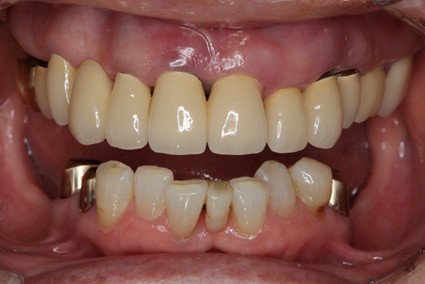

• 治療前

• 治療後